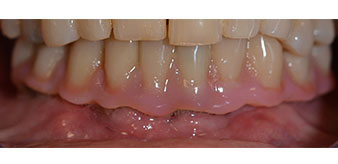

Пациентката е 64-годишна жена с частично обеззъбяване на зъби 38, 33 и 43 и частична долночелюстна протеза (Фиг. 1 и 2).